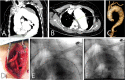

Introduction: The management of thoracic aortic disease involving the ascending aorta, aortic arch and descending thoracic aorta are technically challenging and is an area in constant development and innovation.

Results: A total of 95 patients treated for thoracic aortic diseases in this period, 18 underwent hybrid treatment and entered in this study. The average ages were 62.3 years. The male was present in 66.7%. The technical and therapeutic success was 94.5% e 83.3%. The perioperative mortality rate of 11.1%. There is any death during one-year follow- up. The reoperation rates were 16.6% due 2 cases of endoleak Ia and one case of endoleak II. There is any occlusion of anatomic or extra anatomic bypass during follow up.

Conclusion: In our study, the hybrid treatment of aortic arch disease proved to be a feasible alternative of conventional surgery. The therapeutic success rates and re- interventions obtained demonstrate the necessity of thorough clinical follow-up of these patients in a long time.